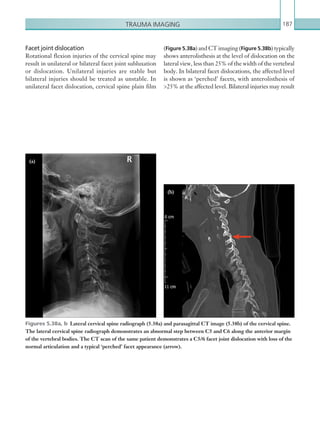

Facet joint dislocation 187

Burst fracture 188